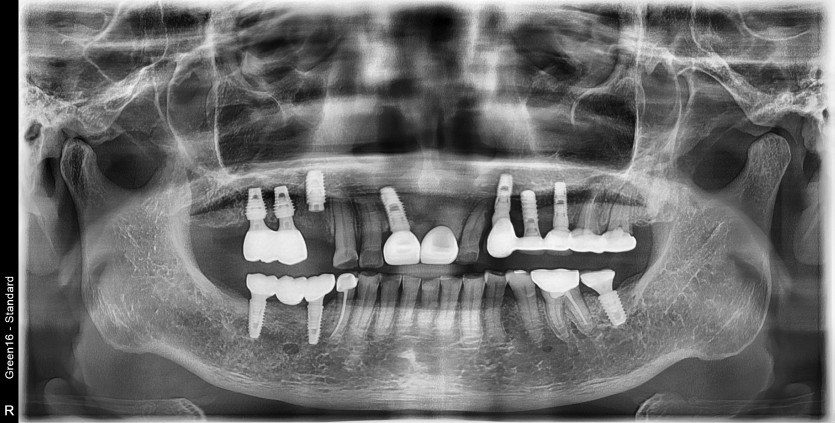

타원임플란트 #14 파절되어 재수술